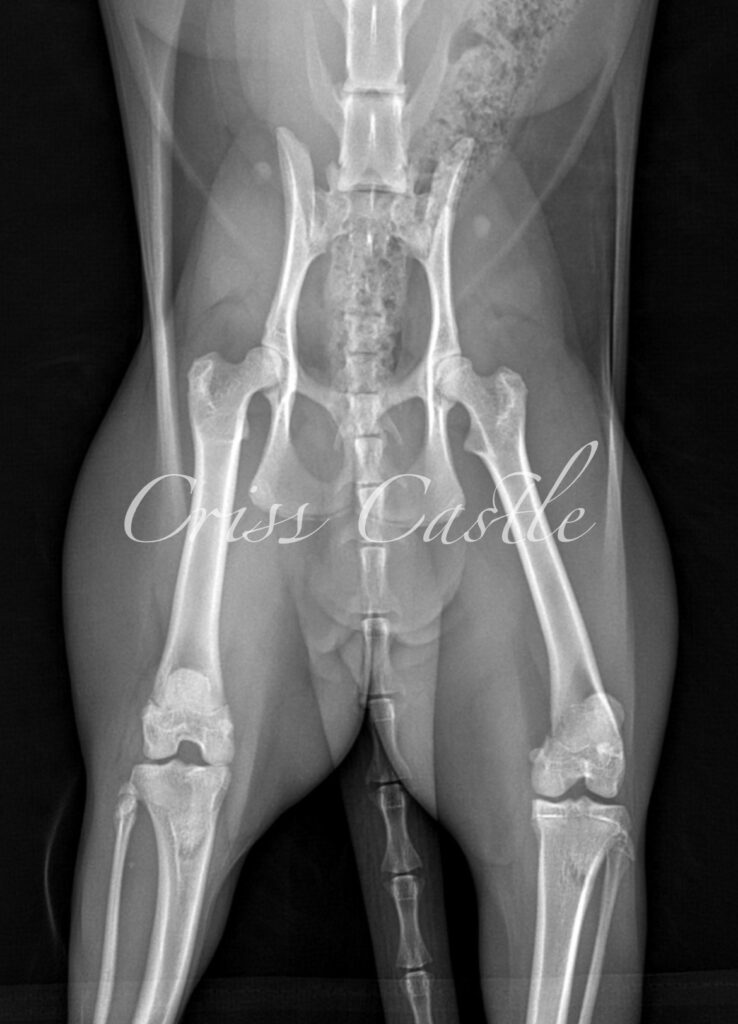

Below are the current hip x-ray results for each Criss Castle breeding cat.

Note that as the cats continue to grow, this page may be updated with new results.